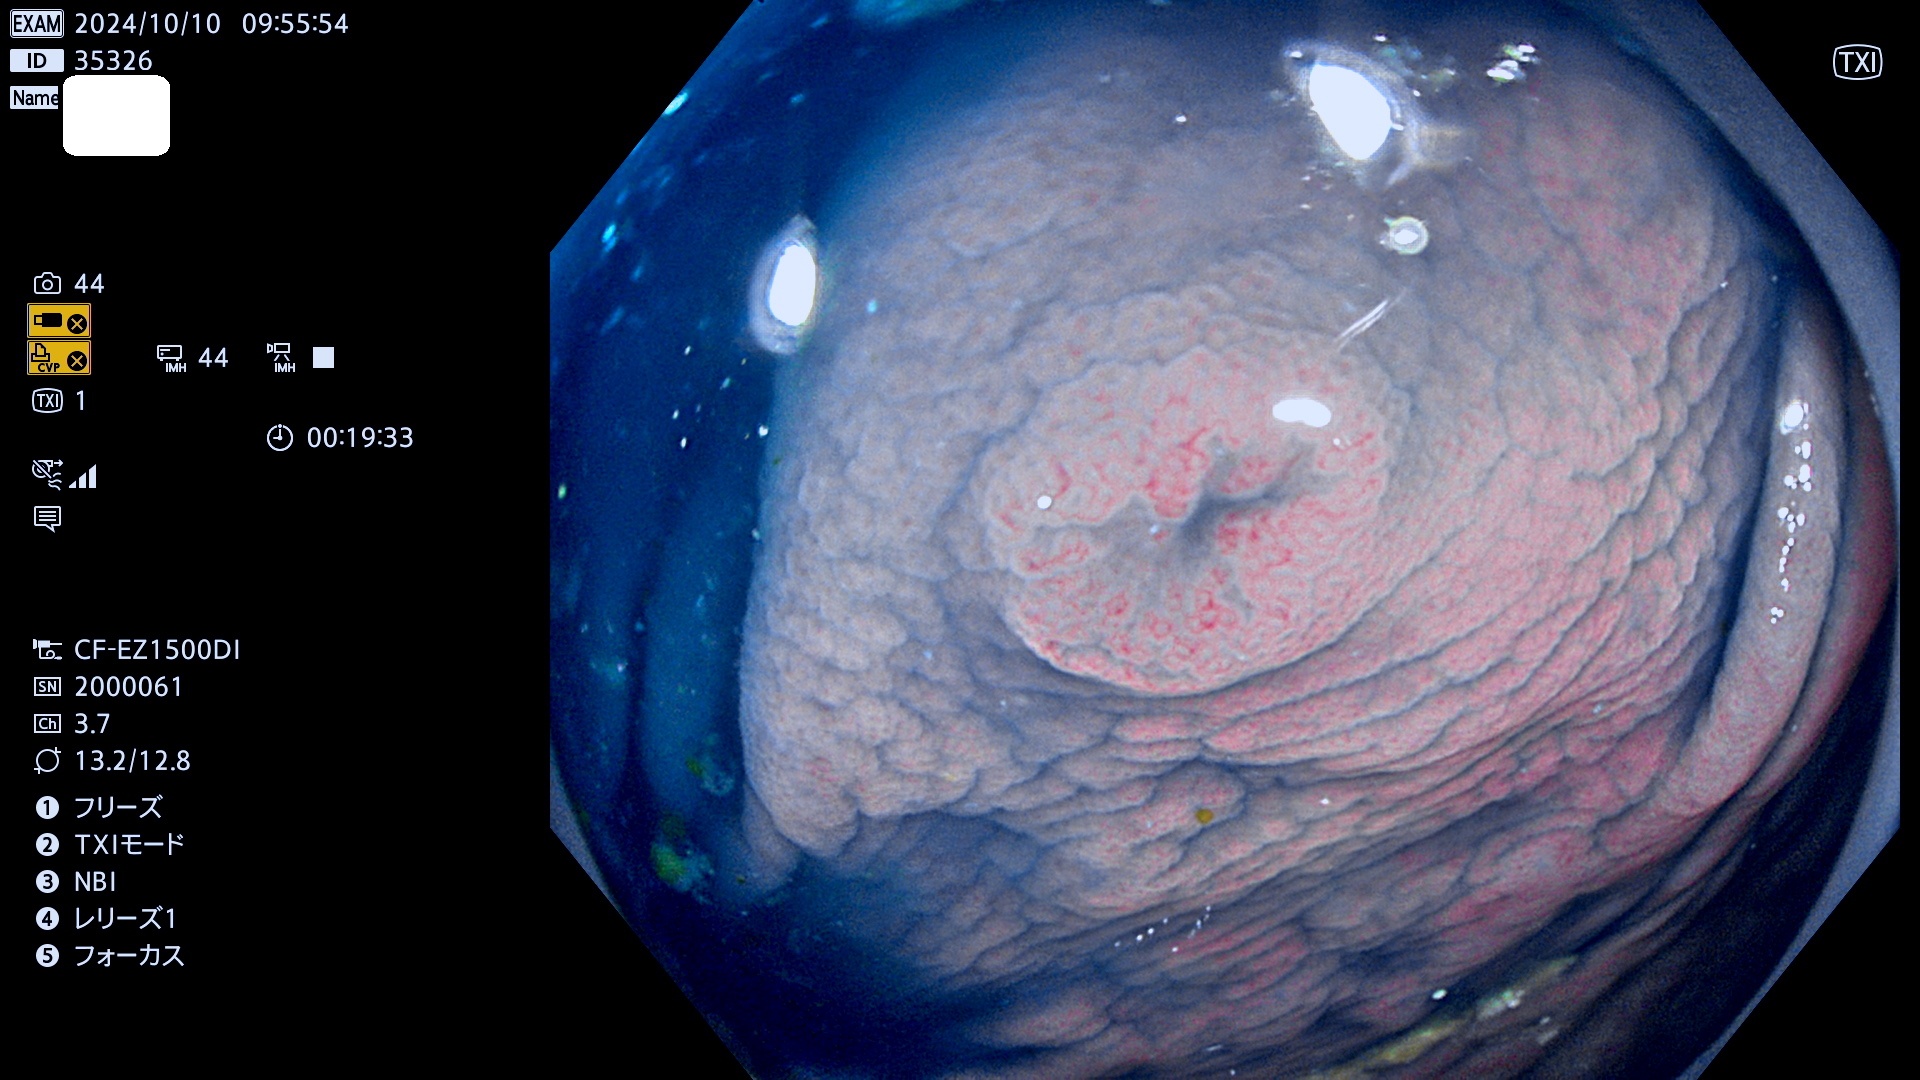

完全に平坦な物をUb、陥凹している物をUcと呼びます。最も発見が難しく危険な病変です。

抽出の対象期間 2024年10月10日〜10月13日の4日間(48件の検査)7件 (7/48=14%)